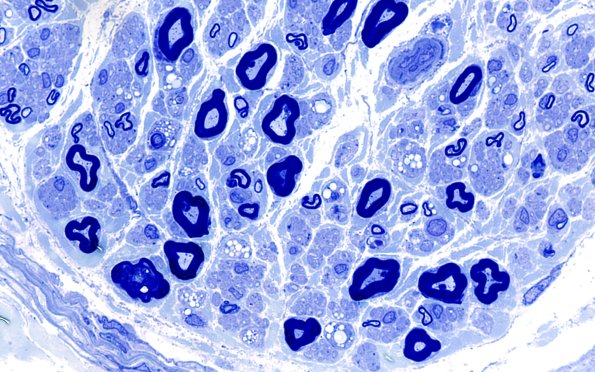

Washington University Experience | PERIPHERAL NEUROPATHY | 4 AXONAL DEGENERATION | 2 Plastic Sections | 19A3 Lipid xs nerve (Case 19) 100X 4

The large amount of lipid in residual and reactive Schwann cells is somewhat unusual. It could represent the simultaneous loss of an axon population or the failure to complete the cycle of handing off debris to a population of macrophages but that is speculative.